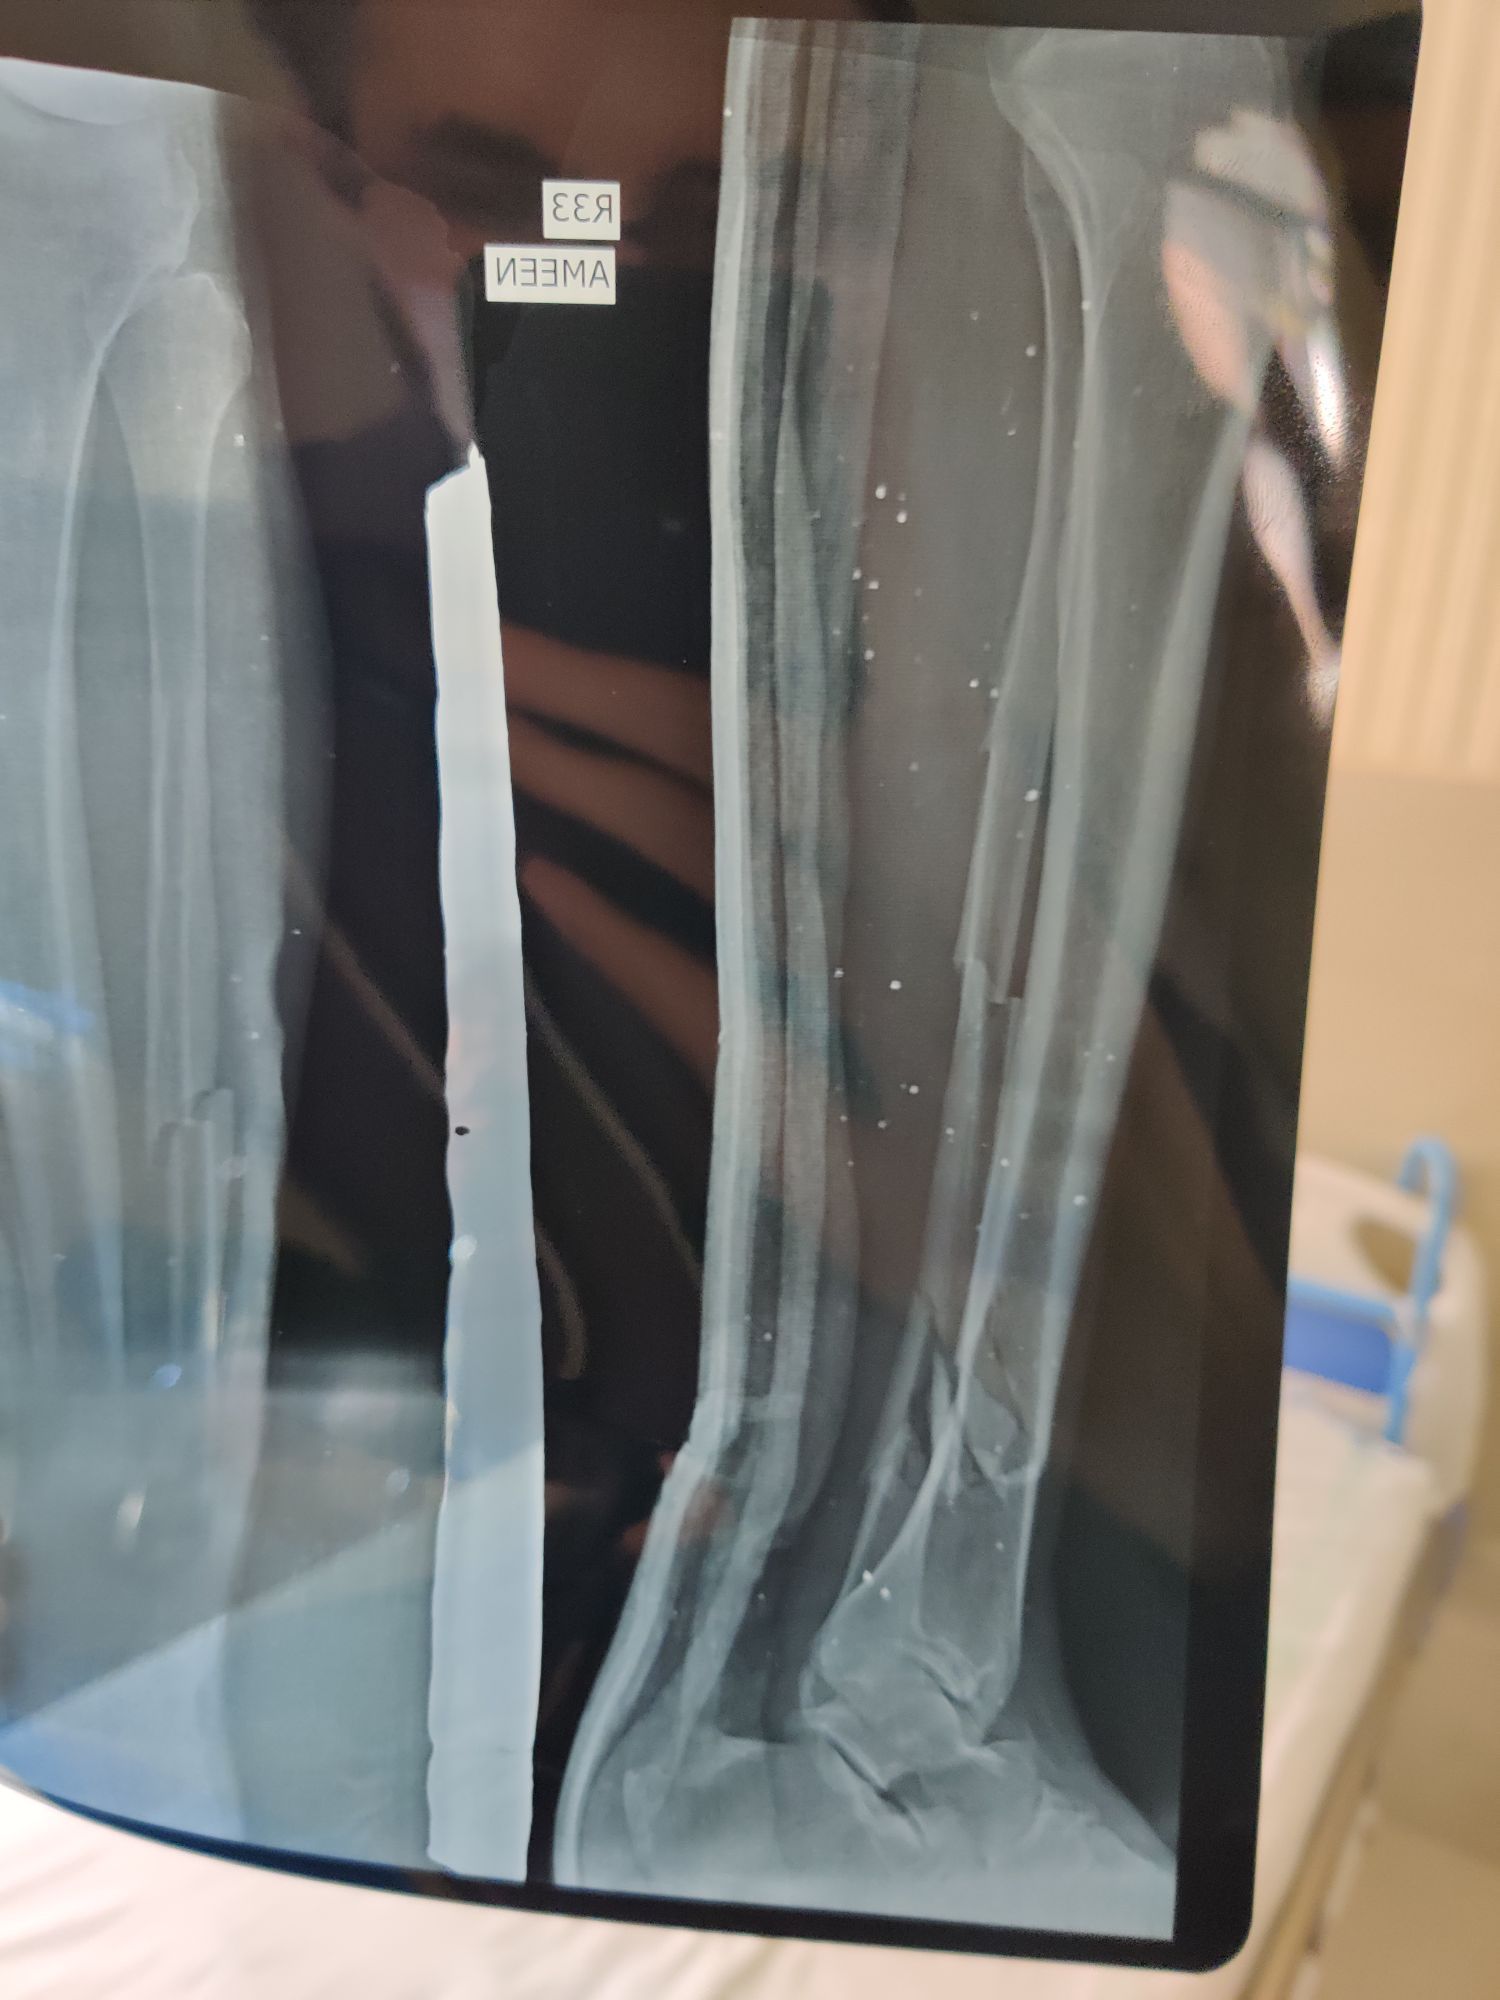

Tibia + Fibula fracture

Tibia

Fibula